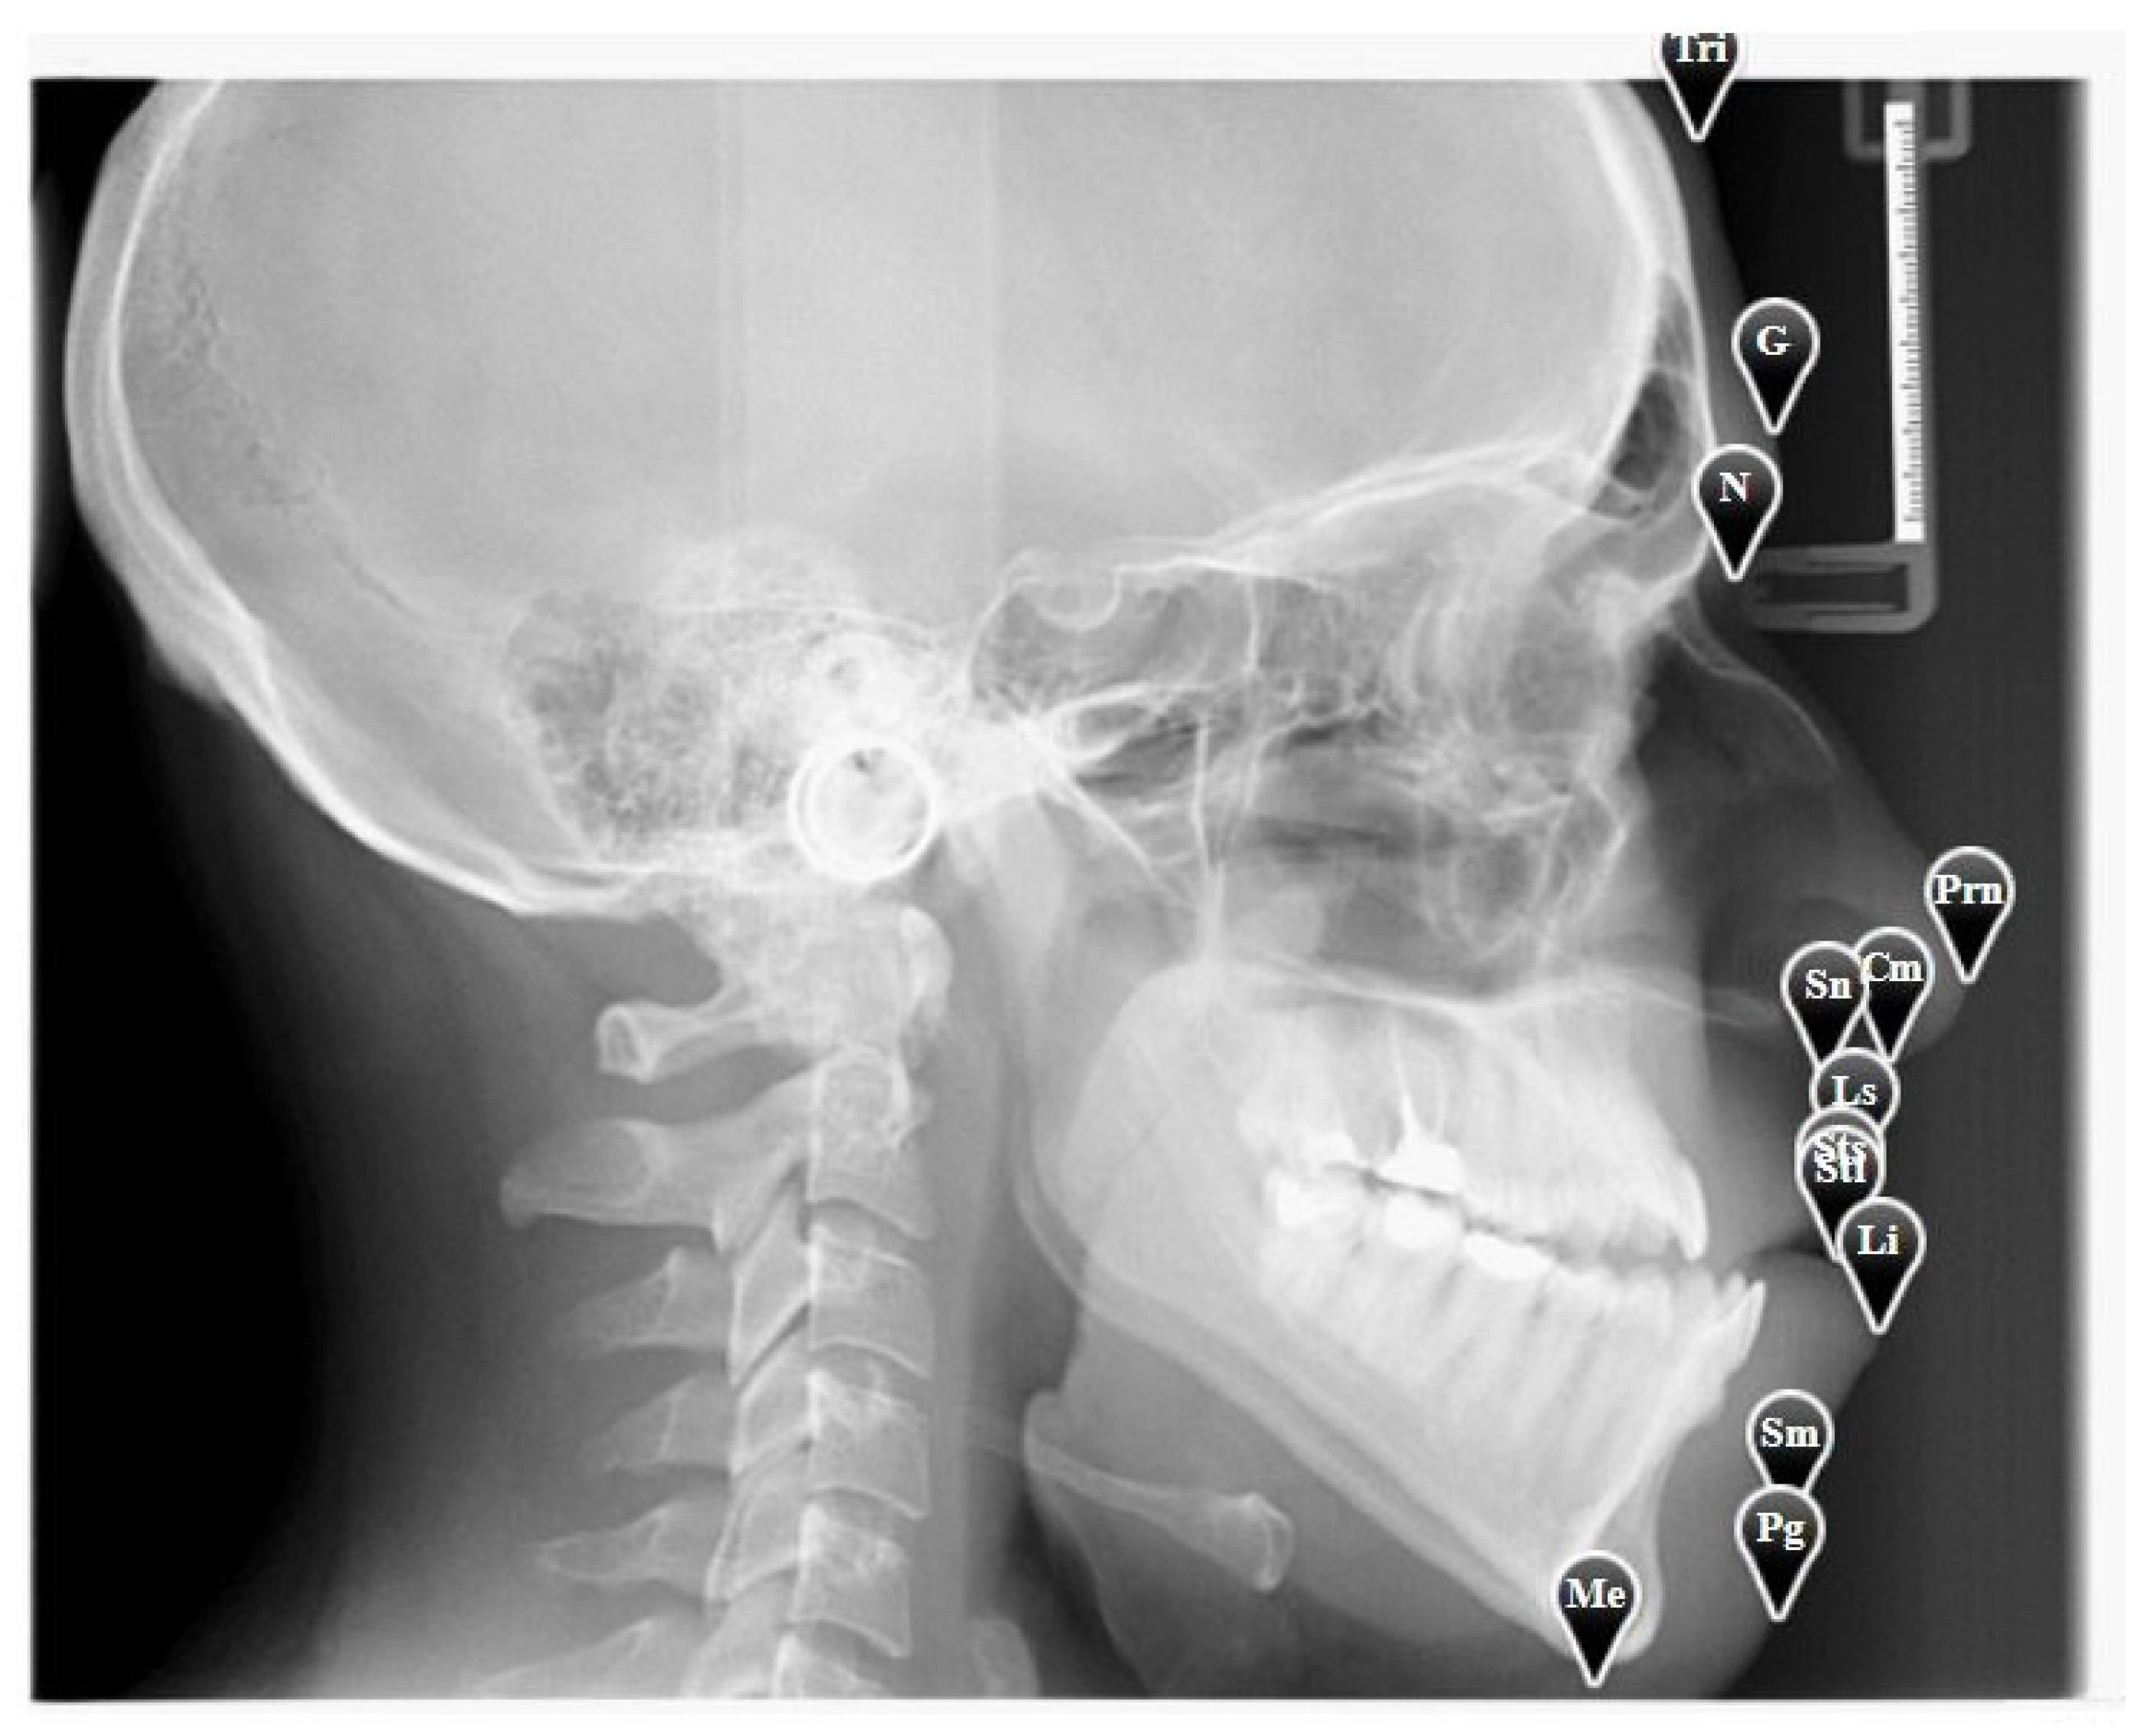

In this study, we use 13 landmarks from the soft tissue area as shown in Table 1.

The user should click “Annotations” to start annotating the above landmarks, or if he has already done so, he can update those annotations easily. For illustration purposes, we show a sample X-ray image with the expert annotations in Figure 4.

Figure 4. A sample X-ray image with annotation.

Table 1. The set of soft tissue landmarks.

Landmark NameDescription

TriIt is the sagittal middle point of the forehead that borders the hairline

GIt is the most anterior point of the forehead’s central line

NIt is the point in the middle line that is placed at the root of the nose

PrnIt is the most noticeable part of the nose’s tip

CmIt is the nose’s most inferior and anterior point

SnIt’s the junction of the upper lip and the columella

LsIt’s the place where the upper lip’s mucocutaneous limit is indicated

StsIt is the upper lip’s most inferior point

StiIt is the upper lip’s most superior point

LiIt is the place where the lower lip’s mucocutaneous limit is indicated

SmThe inferior sublabial concavity’s deepest point lies here

PgIt is the chin’s most anterior point

MeIt is the most inferior point of the chin’s inferior edge